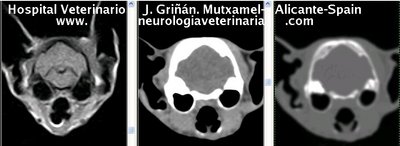

Se muestran cortes transversales de Resonancia Magnética (imagen a la izqda del lector), TC contrastado para tejidos blandos (imagen del centro) y TC contrastado para tejidos duros (imagen de la derecha del lector).

Nótese como la Resonancia supera al TC en el contraste de tejidos blandos (encéfalo y médula espinal) y en el de líquidos (ojo y líquido cefalorraquídeo), mientras que el TC supera a la resonancia en el contraste de tejidos duros (hueso) y aire (senos, cavidad nasal y bullas)